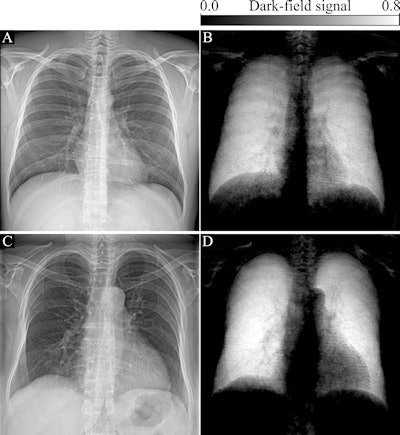

In attenuation-based radiography, dense structures generate a high signal, while in dark-field imaging, the small-angle scattering in lung tissue generates a high signal. Because dark-field x-ray imaging excludes unscattered photons, the space around the lungs appears dark (because there is no material there to scatter photons).

Importantly, the researchers developed a prototype that acquired both attenuation-based and dark-field chest radiographs simultaneously. Each patient's total dark-field signal was correlated with his or her lung volume, and the dark-field coefficient was correlated with age, sex, weight, and height.

The researchers found normal human lungs on dark-field chest x-ray imaging produced high signal, while the surrounding osseous structures had low signal and soft tissue produced no signal. The average total dark-field signal intensity over all participants for the entire lung was (17 ± 4) × 10-3 m2 and the total signal demonstrated a positive correlation with lung volume (r = 0.61, p < 0.001).

"Because of the nature of signal generation in dark-field imaging, bone structures and soft tissue generate only a minimal dark-field signal compared with lung tissue. This feature allows for a detailed depiction of lung tissue without impairment by surrounding structures. We found that the quantitative x-ray dark-field coefficient based on the total dark-field signal and lung size is independent from the subject's characteristics," the researchers wrote.